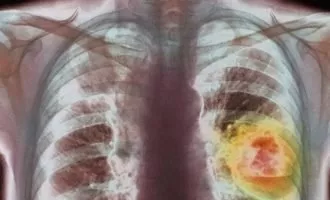

علمی آزمایش تکنیک اصلاح ژنتیکی CRISPR روی یک بیمار مبتلا به سرطان ریه در چین

بنابر گزارش نشریه نیچر، دانشمندان چینی برای نخستین بار در دنیا سلول های دستکاری شده با تکنیک اصلاح ژنوم موسوم به CRISPR را به یک بیمار ...

تکنولوژی اولین دستکاری ژنتیکی در سلول های انسانی به روش CRISPR؛ نبرد با سرطان ریه

به گزارش نشریه «Nature» قرار است در ماه آگوست، برای اولین بار دستکاری ژنتیکی سلول های انسانی به روش CRISPR در کشور چین به انجام برسد. ...